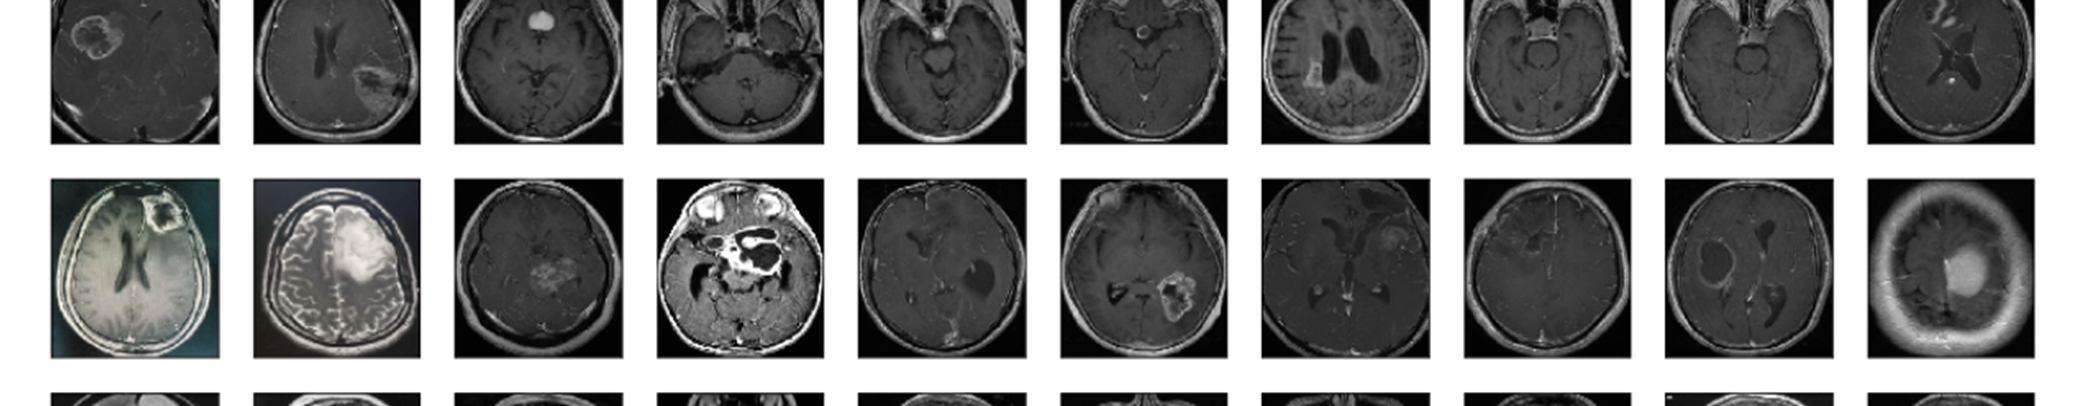

Figure2: Dataset of MRI scans containing tumors

Data augmentation is a technique used in data analysis to expand the volume of information by inserting reproductions of pre existing data that have been significantly altered or newly created synthetic data from preexisting data. Before data augmentation, the dataset contained 155 positive and 98 negative samples, producing 253 sample pictures. After data augmentation, a new dataset is created with 2065 example photographs from 1085 positive and 980 sample photos.